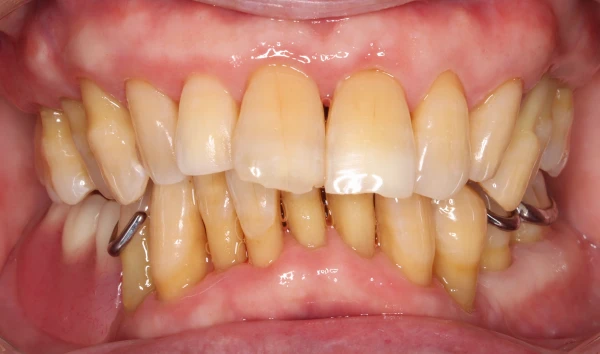

04

抜歯になった際の

インプラントインプラントも対応

歯周病により破壊された、歯茎や骨を人工骨や成長因子などを用いて再生させる治療方法です。将来的に抜歯となるリスクの高い歯などを歯周組織を再生させ、歯を長持ちさせることを目的とします。歯周病でダメになった歯をどうしても残したい方、歯ぐきや歯槽骨を元に戻して歯の寿命をしっかり伸ばしたい方に適応される治療方法です。

インプラント

という選択肢

歯を失った場合、自然な噛み心地を取り戻せる治療としてインプラントをご提案しています。周囲の歯に負担をかけず、見た目・機能ともにしっかり回復できる選択肢です。